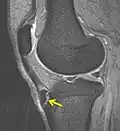

IRM d'un Osgood-Schlatter- Radiographie d'un Osgood-Schlatter